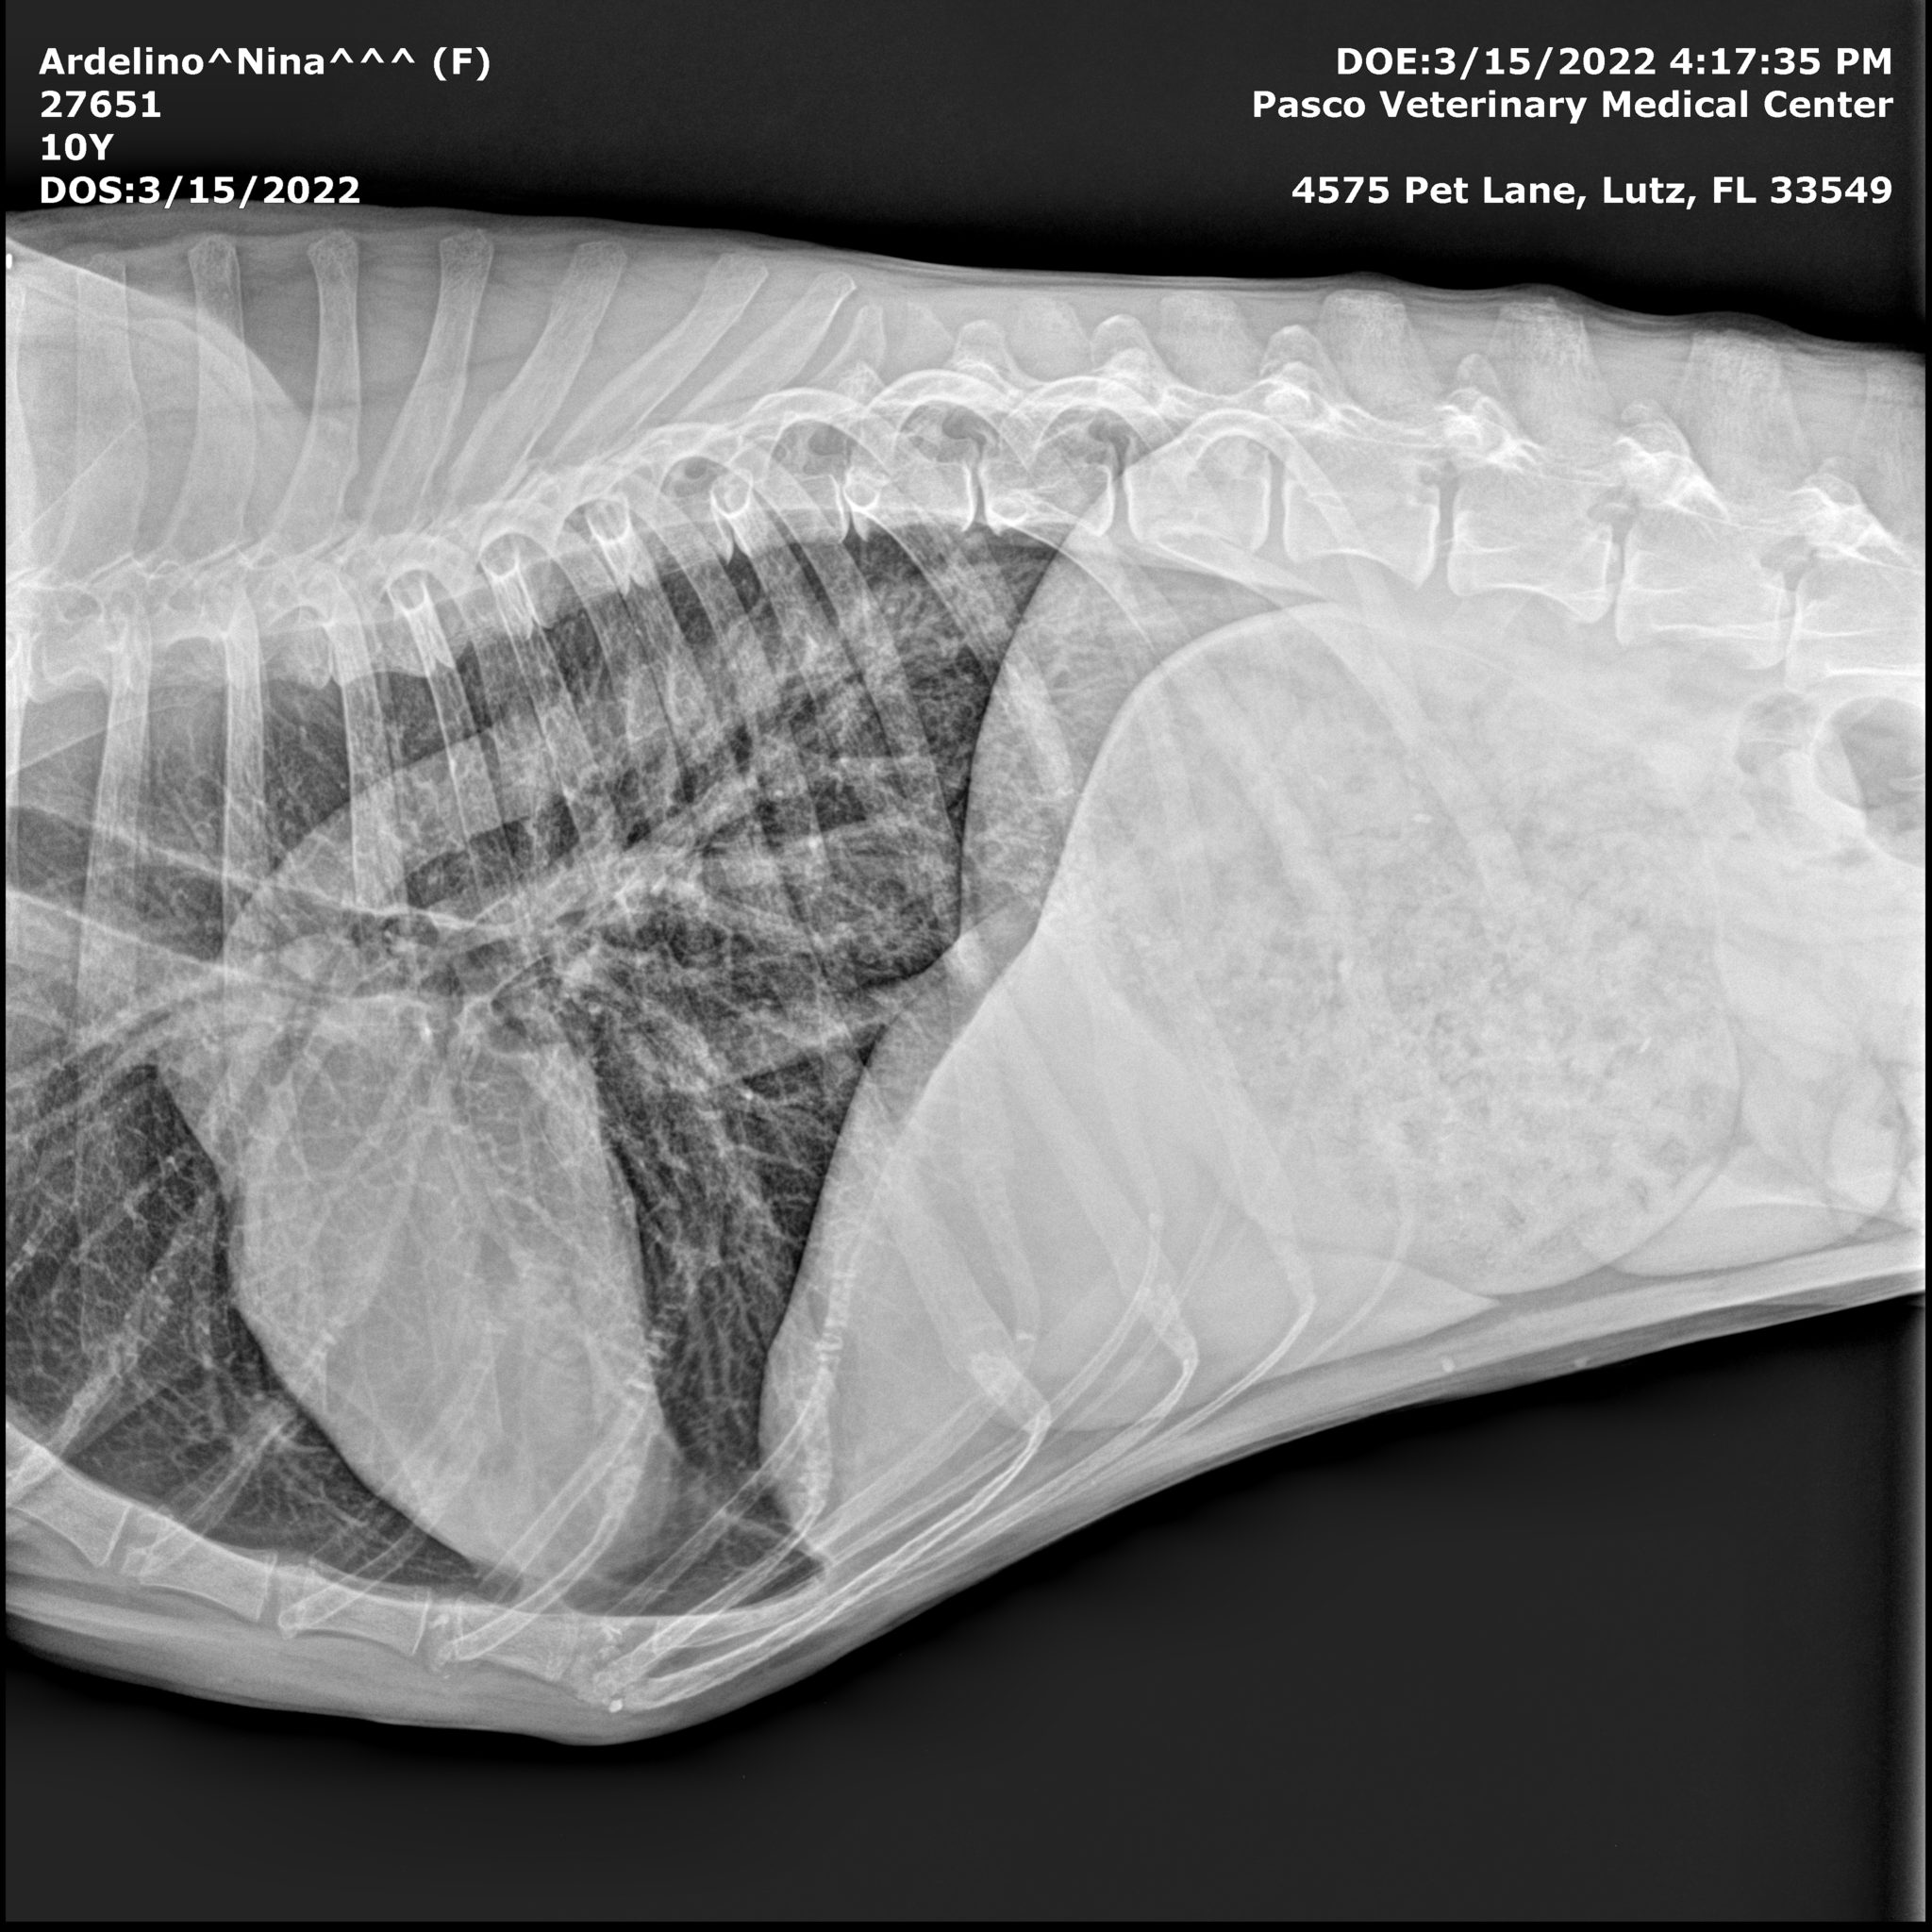

Here are Nina’s X-rays, showing no metastasis, no spread of cancer 22 months post diagnosis of osteosarcoma in dogs:

The results were what we’d hoped for! No Metastasis! Once again there was NO SPREAD of cancer anywhere else in her body.

The tumor had grown to the size of a grapefruit, and was cutting off circulation to her foot. It had also started to seep fluids, through a small sore on the surface of the growth. This meant that we would once again run all the diagnostic tests again to see if, after 22 months, the cancer had metastasized.